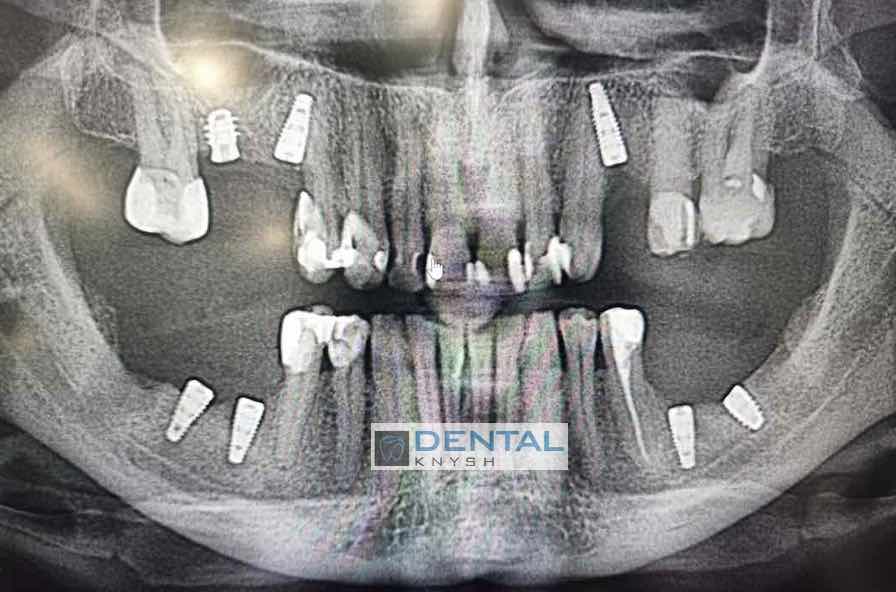

Сканы КТ имплантации зубов, 2026-04-18

Скан КТ, 2026-04-18

Сканы КТ имплантации зубов, 2026-04-18

Скан КТ имплантации зубов, 2026-04-17

Сканы КТ имплантации зубов, 2026-04-18

KT: имплантация зубов DentalKnysh, 2025-01-03, сканы

KT: имплантация зубов DentalKnysh, 2025-01-03, сканы

KT: имплантация зубов DentalKnysh, 2025-01-03, сканы

С 2023-09-05 по 2023-09-09 сканы КТ от 6 до 12 имплантов в DentalKnysh (4 фото):

Синуслифтинг и имплантация зубов, 6 имплантов, all-on-6, КТ скан 1, 2023-08-31

Фото отчет Имплантация зубов, 6 имплантов, КТ скан 3, 2023-08-31

Фото отчет Имплантация зубов, 8 имплантов, all-on-4, КТ скан 1, 2023-08-31